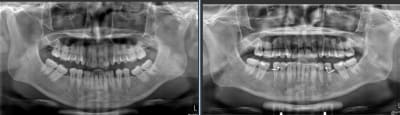

Patient vue aujourd'hui. Quatre mois de traitement .

Patient qui ne vient pas au rendez vous et se plaint de tout, bref je doute que ça se soit bien passer en baguant toutes les dents :-)

Aujourd'huit c'était la journée. Patient pas venue depuis deux mois , appareillage en place depuis un peut mois de trois mois, compter encore un ou deux mois et il y auras assez d'espace pour poser les implants.